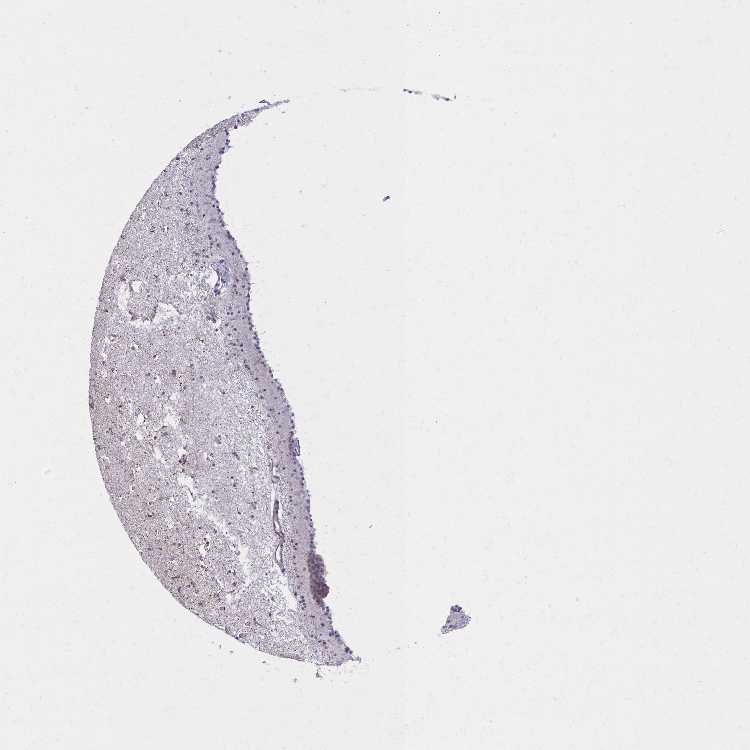

CAUDATE - Antibody stainingi

Antibody staining in the annotated cell types in the current human tissue is reported as not detected, low, medium, or high, based on conventional immunohistochemistry profiling in selected tissues. This score is based on the combination of the staining intensity and fraction of stained cells.

Each image is clickable and will lead to virtual microscopy that enables deeper exploration of all samples and also displays staining intensity scores, fraction scores and subcellular localization as well as patient and tissue information for each sample.

Antibody HPA059918Antibody HPA065064

Glial cells LowNot detected

Neuronal cells MediumLow